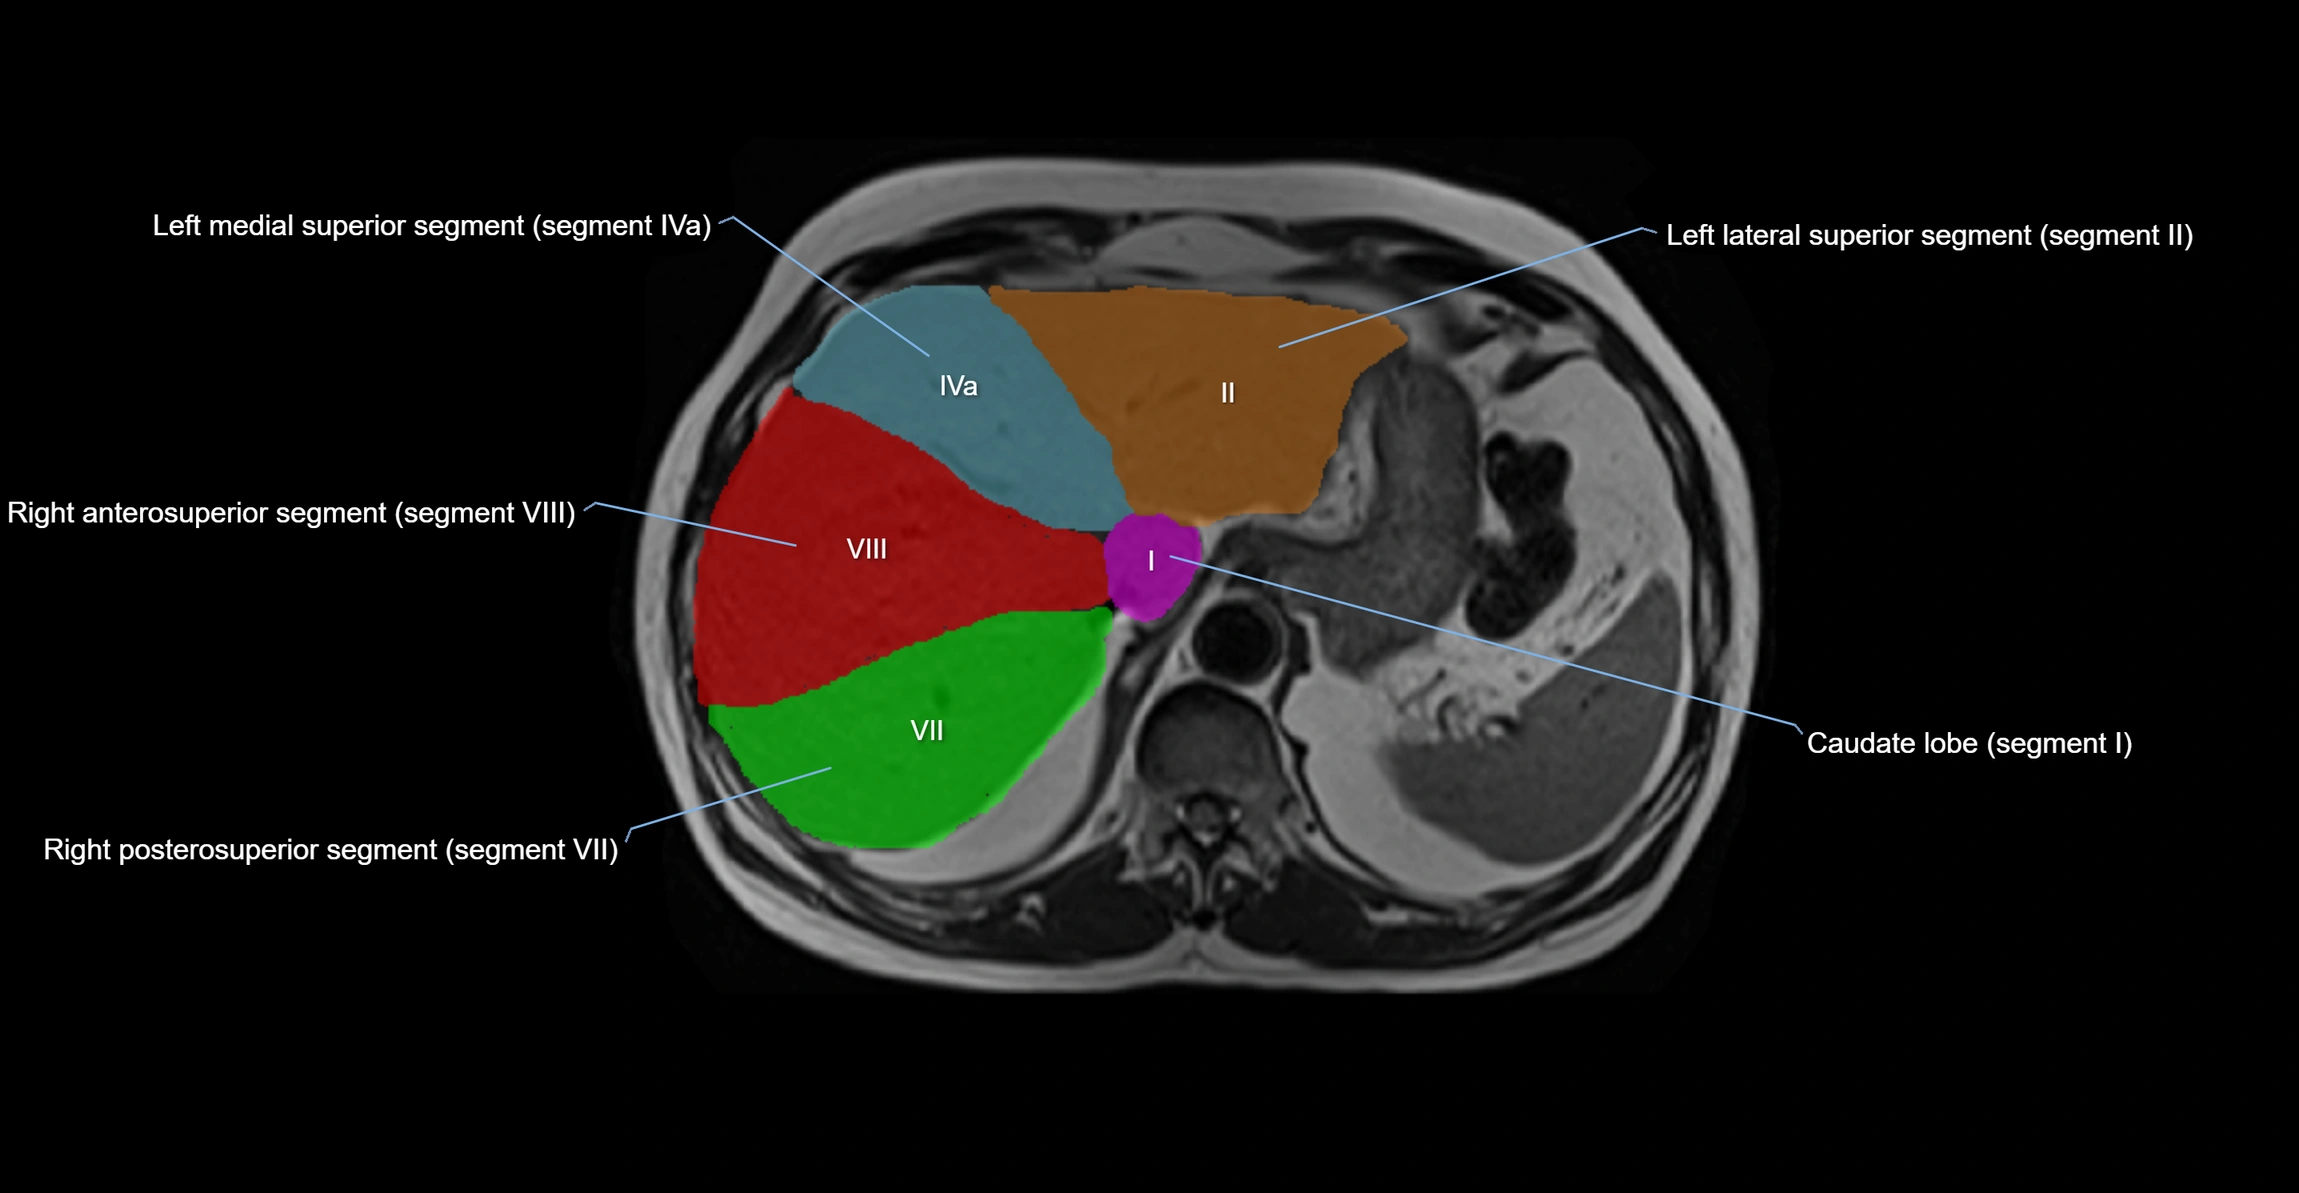

The caudate lobe of the liver is a distinct anatomical subdivision of the liver, designated as segment I in Couinaud’s classification. It lies on the posterior surface of the liver, between the fissure for the ligamentum venosum (left boundary) and the groove for the inferior vena cava (IVC) (right boundary). Superiorly, it is related to the posterior liver surface, and inferiorly it is separated from the left lobe by the porta hepatis.

The caudate lobe is unique because it receives dual portal venous and arterial inflow from both the right and left portal veins and hepatic arteries. It also has independent venous drainage directly into the IVC via multiple small hepatic veins, unlike other lobes that drain through the three main hepatic veins.

This anatomical autonomy makes the caudate lobe especially significant in liver surgery, transplantation, and hepatic venous outflow obstruction syndromes (e.g., Budd–Chiari syndrome). Enlargement of the caudate lobe is a characteristic imaging feature in chronic liver disease and cirrhosis.